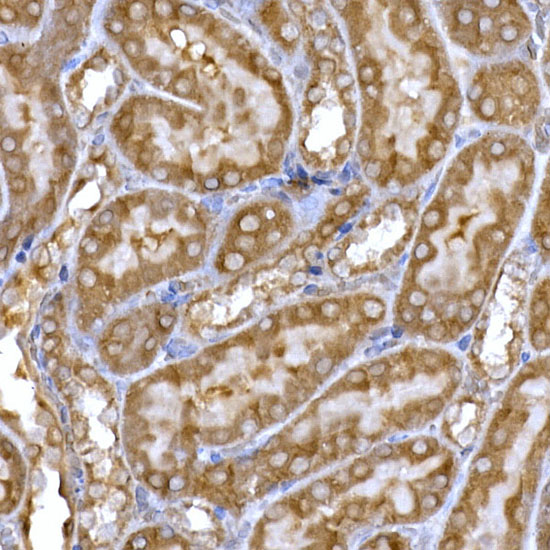

The antibodies are generated in various hosts and react to antigens of different species like human, mouse, rat, rabbit or zebrafish. The antibodies are validated for multiple applications, including immunohistochemistry, western blot, immunoprecipitation, ELISA and flow cytometry, to ensure reliable performance for your research needs.